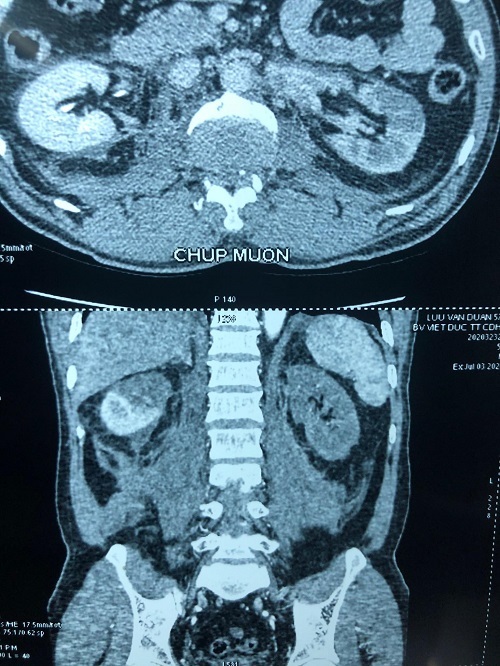

Bệnh nhân L.V.D. 57 tuổi, được chuyển từ bệnh viện tuyến tỉnh Hải Dương lên cấp cứu tại Bệnh viện Hữu nghị Việt Đức (Hà Nội) sau tai nạn xe máy.

Thực hiện chụp chiếu, các bác sĩ phát hiện thận bên phải người bệnh có huyết khối động mạch cực trên, mất phần cấp máu cho cực trên, thận bên trái thiếu máu hoàn toàn, chức năng thận giảm, có biểu hiện suy thận.

Người bệnh đã được hội chẩn liên khoa Tiết niệu - Tim mạch - Ghép tạng, bác sĩ quyết định mổ ngay để cứu sống thận bên trái, tránh suy thận do đa chấn thương.

Thông thường, với những tổn thương tắc động mạch thận, phẫu thuật sớm từ giờ thứ 6-8 sau tai nạn mới có thể cứu được thận. Tuy nhiên, trường hợp này khi được chuyển vào phòng mổ đã bước sang giờ thứ 24, quá thời gian vàng cho một ca ghép thận tự thân.

Các bác sĩ cho biết, nếu bệnh nhân không có biểu hiện suy thận, có thể không ghép thận tự thân và để bệnh nhân sống bằng thận còn lại. Nhưng trường hợp ông D. đã có dấu hiệu suy thận, bác sĩ bắt buộc phải tiến hành ghép thận tự thân để hai thận vẫn bổ sung chức năng cho nhau.

Nhóm phẫu thuật đã thực hiện song song hai kíp rửa - ghép thận trái; kiểm tra các tạng trong bụng, cơ hoành và bảo tồn thận phải.

Quả thận trái sau khi được lấy nguyên vẹn khỏi cơ thể đã được rửa bằng dung dịch custodial, bơm dung dịch tiêu huyết khối, hy vọng đẩy máu cục trong các mạch máu nhỏ bên trong quả thận. Khoảng 30 phút sau rửa, thận có màu trắng và đã được ghép vào hố chậu trái.

Sau sáu tiếng, ca mổ thành công. Mười ngày sau phẫu thuật, chức năng thận của người bệnh đã trở lại bình thường.

PGS Đỗ Trường Thành, Trưởng khoa Phẫu thuật Tiết niệu, người chỉ huy ca mổ, cho biết, trường hợp này là một điều kỳ diệu. Quả thận của bệnh nhân mặc dù bị thiếu máu rất lâu nhưng các mạch máu trong thận không bị tắc lại, thận sau rửa không tím đen.